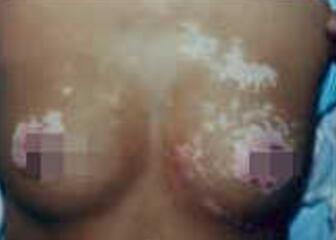

胸部白癜风一般有哪些症状?白癜风发病部位会遍及全身,白斑如果不治疗,很多的患者都担心太过大的面积,会影响外在的面貌。成都白癜风医院医生表示,很多的患者较初白斑都会出现在背部、胸部等地方,尤其就是女性患者更好发于胸部背带紧勒的地方。

1、胸部白癜风是会有皮肤浅白色的色素脱失斑,形状近似圆形、椭圆或是不规则形。通常情况下,胸部白癜风的患者不会有明显的自觉反应,因为白斑出现以后没有痛痒感。

2、白斑是会因为周围有色素沉着而易与正常的皮肤进行区分。另外,胸部白癜风的患者的患处皮肤对于阳光的敏感度会提升,只要稍微接受了太阳照射,皮肤就是会有变红的症状表现,更是有甚者会出现水疱等。

3、白斑多数对称分布,亦有不少的胸部白斑病损害沿神经段排列。白斑病的症状除皮肤损害外,亦可累以及部分粘膜。

4、胸部有毛发的白癜风患者是可发现毛发变白或正常,但是皮损无其它变化,亦无自觉症状。由于缺乏色素保护的作用,曝晒后引起灼痛,红班及水疱。